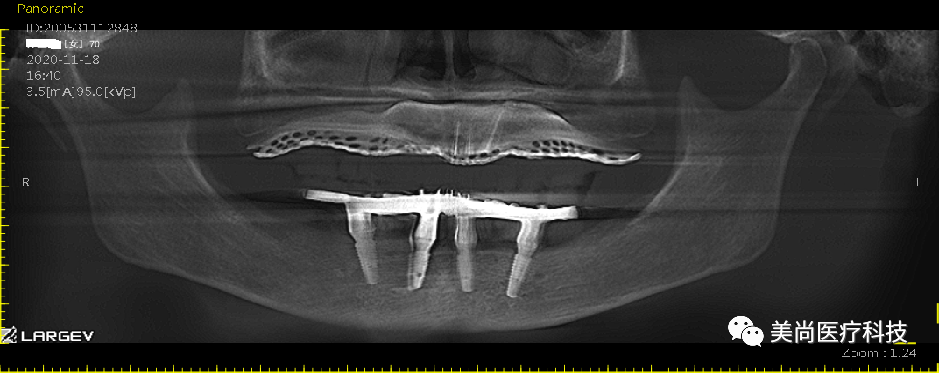

取模即刻负荷戴牙

永久修复

戴牙完成